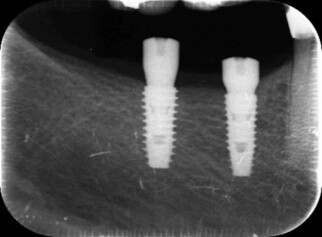

| 0112 #15 右上第二小臼齒 |

![]() |